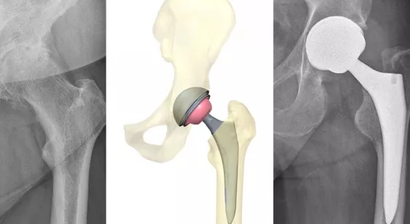

Hüftprothese

Ich habe mich innerhalb meines Fachgebietes auf den künstlichen Gelenkersatz von Hüft- und Kniegelenk, arthroskopische Eingriffe sowie die Fuß- und Handchirurgie spezialisiert. Natürlich biete ich meinen Patienten darüber hinaus auch alle weiteren Leistungen der modernen Orthopädie an.